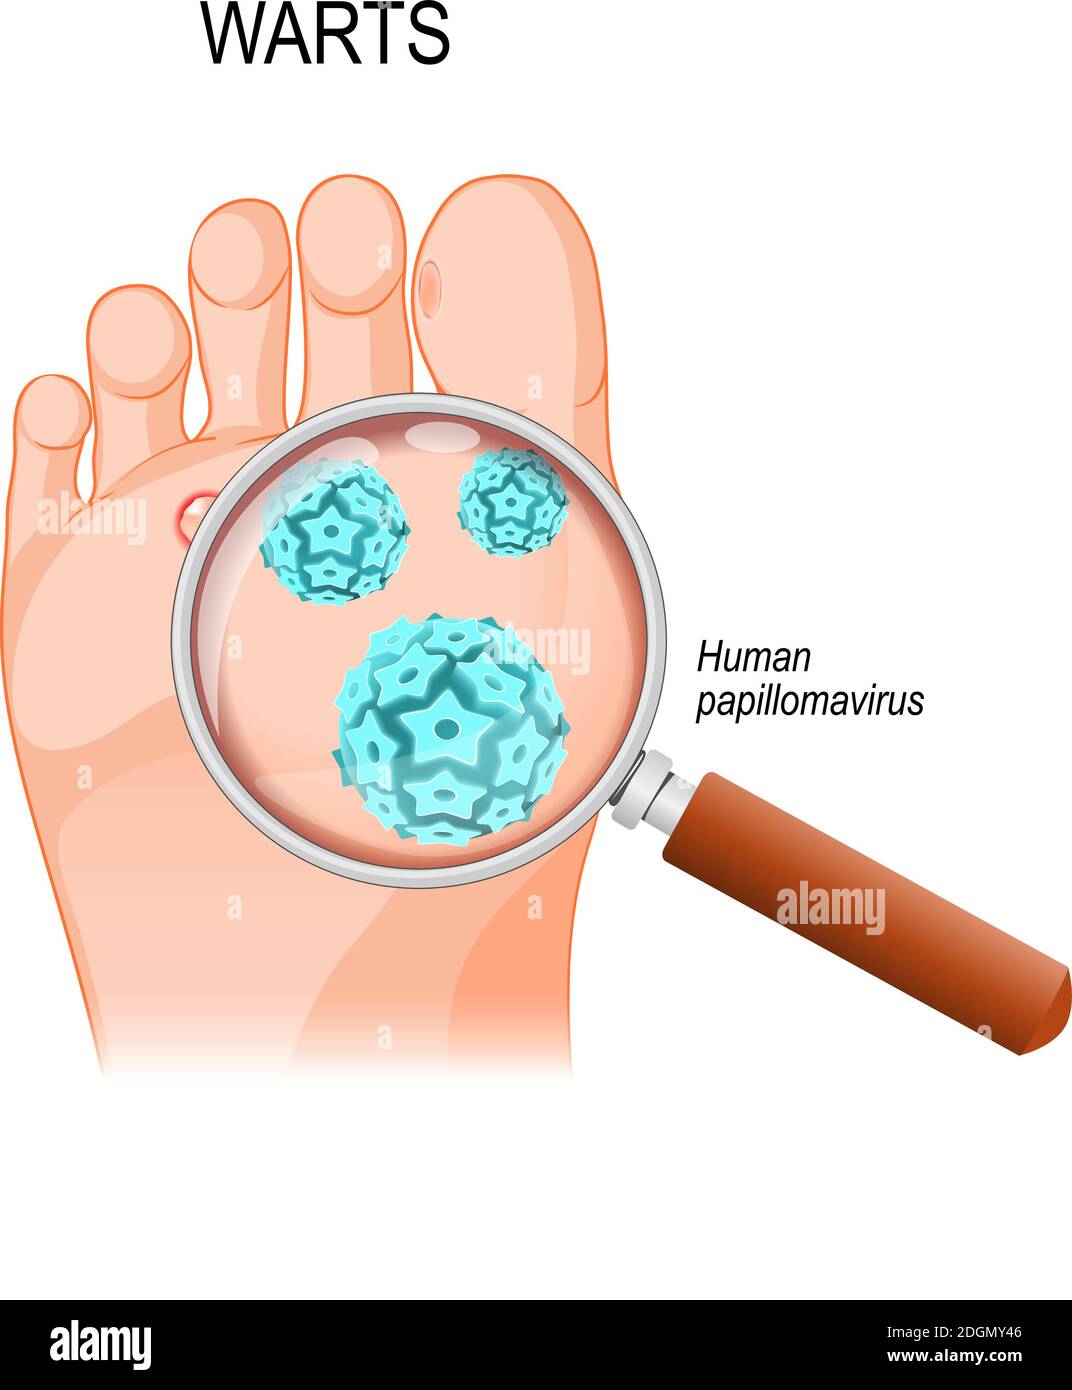

RF2DGMY46–Les verrues du pied sont causées par une infection par un type de virus du papillome humain. Gros plan du HPV